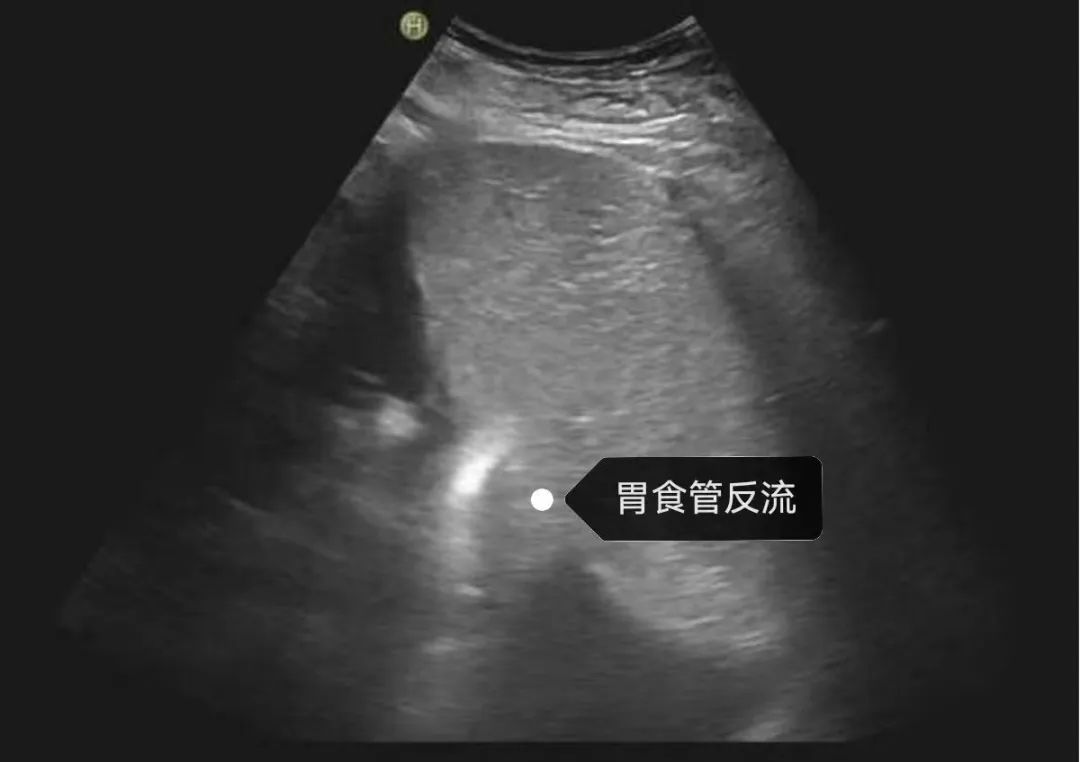

4.功能性病变:胃食管反流、胃十二指肠反流、胃下垂等。

6.胃动力学评估(胃窦容积变化、胃蠕动波、返流评价)。

典型病例分享